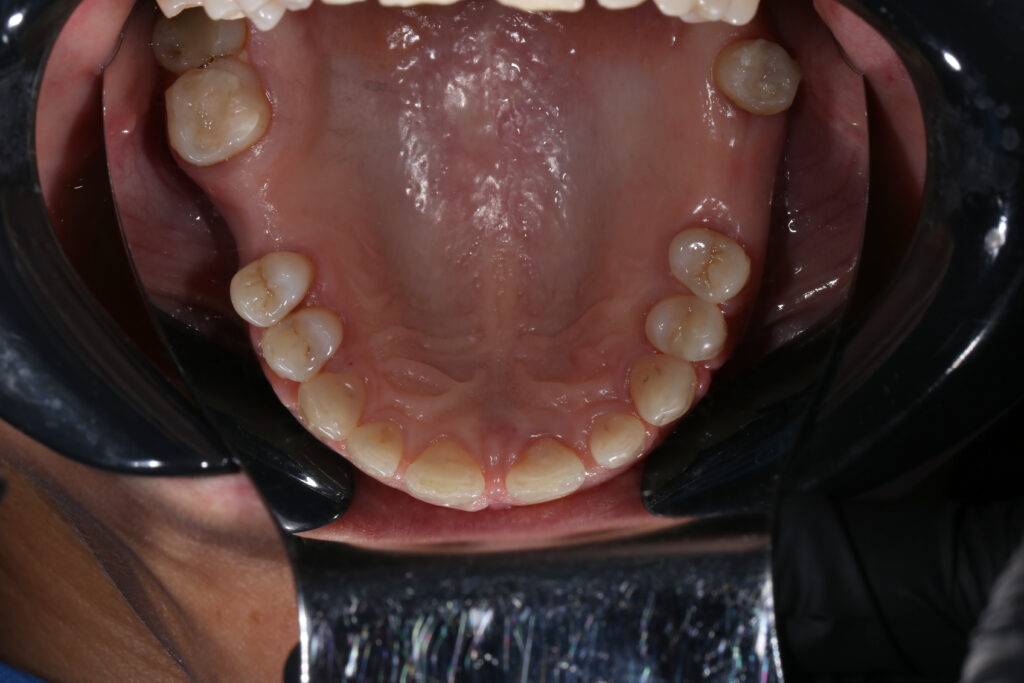

Ситуация до лечения

Из-за множественных давних удалений жевательных зубов, произошла деформация зубных рядов, зубы разъехались в область удаленных, что затрудняло протезирование в момент обращения к ортопеду.

Так же можно отметить сильное снижение высоты прикуса (верхние зубы на 100% перекрывали нижние, что вызывало хроническую травму десны), а также повышенную стираемость твердых тканей зубов, что является следствием повышенной нагрузки, которую много лет испытывали передние зубы, в связи с отсутствием жевательных зубов.

В связи со всеми вышеперечисленными факторами, пациентка нуждалась в тотальной реабилитации.